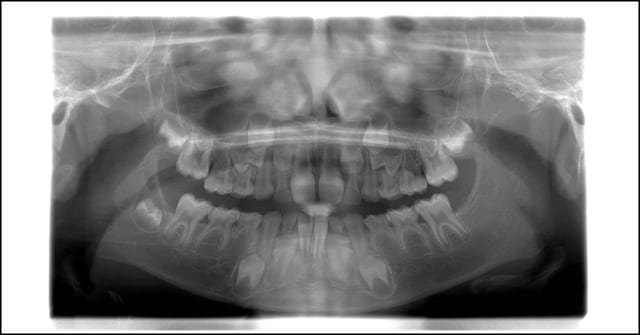

Deux petits patients de 6 ans et demi, jumeaux homozygotes, se présentent à l'instant à mon cabinet. La mère qui suis un traitement ortho/implanto suite à 6 agénésies, me demande vérifier si ses garçons présentent le même problème.

Je fais la pano du premier,

il en manque 8 Le second, je dit " Normalement, il devrait y avoir la même chose si la nature est bien faite". Manqué : la 22 qui manque sur le premier, est belle et bien là pour le second, toutes les autre parfaitement absentes aux mêmes endroits.

Conclusion (hative): Il existe une détermination génétique mais également forcément des facteurs externes qui déterminent l'activation de la fabrication du germe, ou pas.

(Peut être un mix dans les numéro des jumeaux mais vous savez compter des dents)